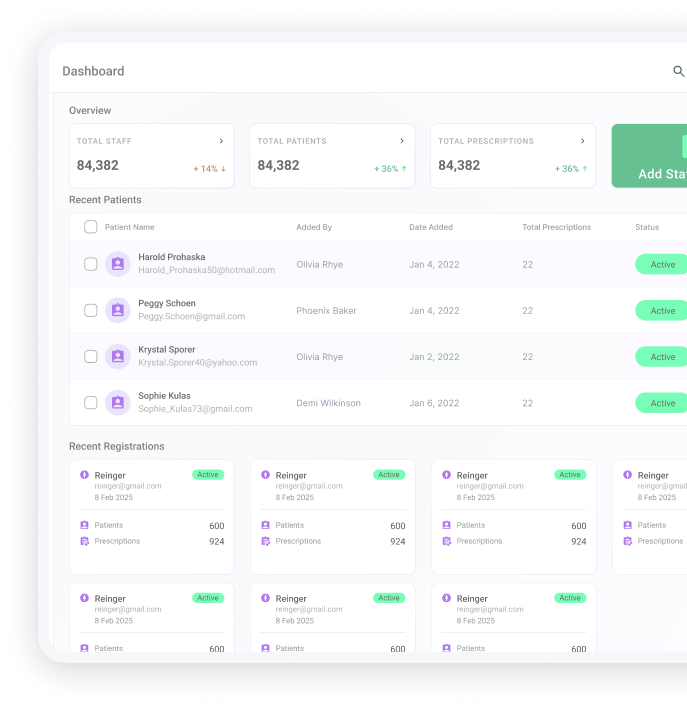

Simplify, Secure, And Streamline Your Patient Care

Our electronic private prescription service allows clinicians to send paperless, secure and completely compliant prescriptions direct to our central dispensary for next day delivery.

Monitor the journey of your prescriptions from being sent to awaiting payment, awaiting dispensing and dispatched

We store patients’ data safely so you can easily repeat prescriptions allowing you to spend more time on your other tasks and with your patients.

More secure than traditional paper prescriptions with no risk of forged or copied prescriptions.

Complete Solution To Electronic Prescribing

Our electronic private prescription service allows clinicians to send paperless, secure and completely compliant prescriptions direct to our central dispensary for next day delivery.

Generate and send prescriptions in seconds with just a few clicks. No handwriting errors, no misinterpretations—just clear, accurate digital scripts.Generate and send prescriptions in seconds with just a few clicks. No handwriting errors, no misinterpretations—just clear, accurate digital scripts.

Generate and send prescriptions in seconds with just a few clicks. No handwriting errors, no misinterpretations.

Complete audit trail and reporting system for all prescriptions issued by clinicians

Benefits of Using Direct RX

Convenience

You can create prescriptions within a few minutes which are sent to our central dispensary immediately for dispatch the same day.

Secure

More secure than traditional paper prescriptions with no risk of forged or copied prescriptions.

Repeat prescriptions

We store patients’ data safely so you can easily repeat prescriptions allowing you to spend more time on your other tasks and with your patients.

Prescription tracking

Monitor the journey of your prescriptions from being sent to awaiting payment, awaiting dispensing and dispatched